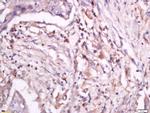

Phospho-CD18 (Thr758) Antibody in Immunohistochemistry (Paraffin) (IHC (P))

Phospho-CD18 (Thr758) Antibody (BS-10462R) in IHC (P)

Formalin-fixed and paraffin embedded human lung carcinoma labeled with Anti-CD18 (Thr758) Polyclonal Antibody, Unconjugated (bs-10462R) at 1:200 followed by conjugation to the secondary antibody and DAB staining. {{ $ctrl.currentElement.advancedVerification.fullName }} 验证信息 View more